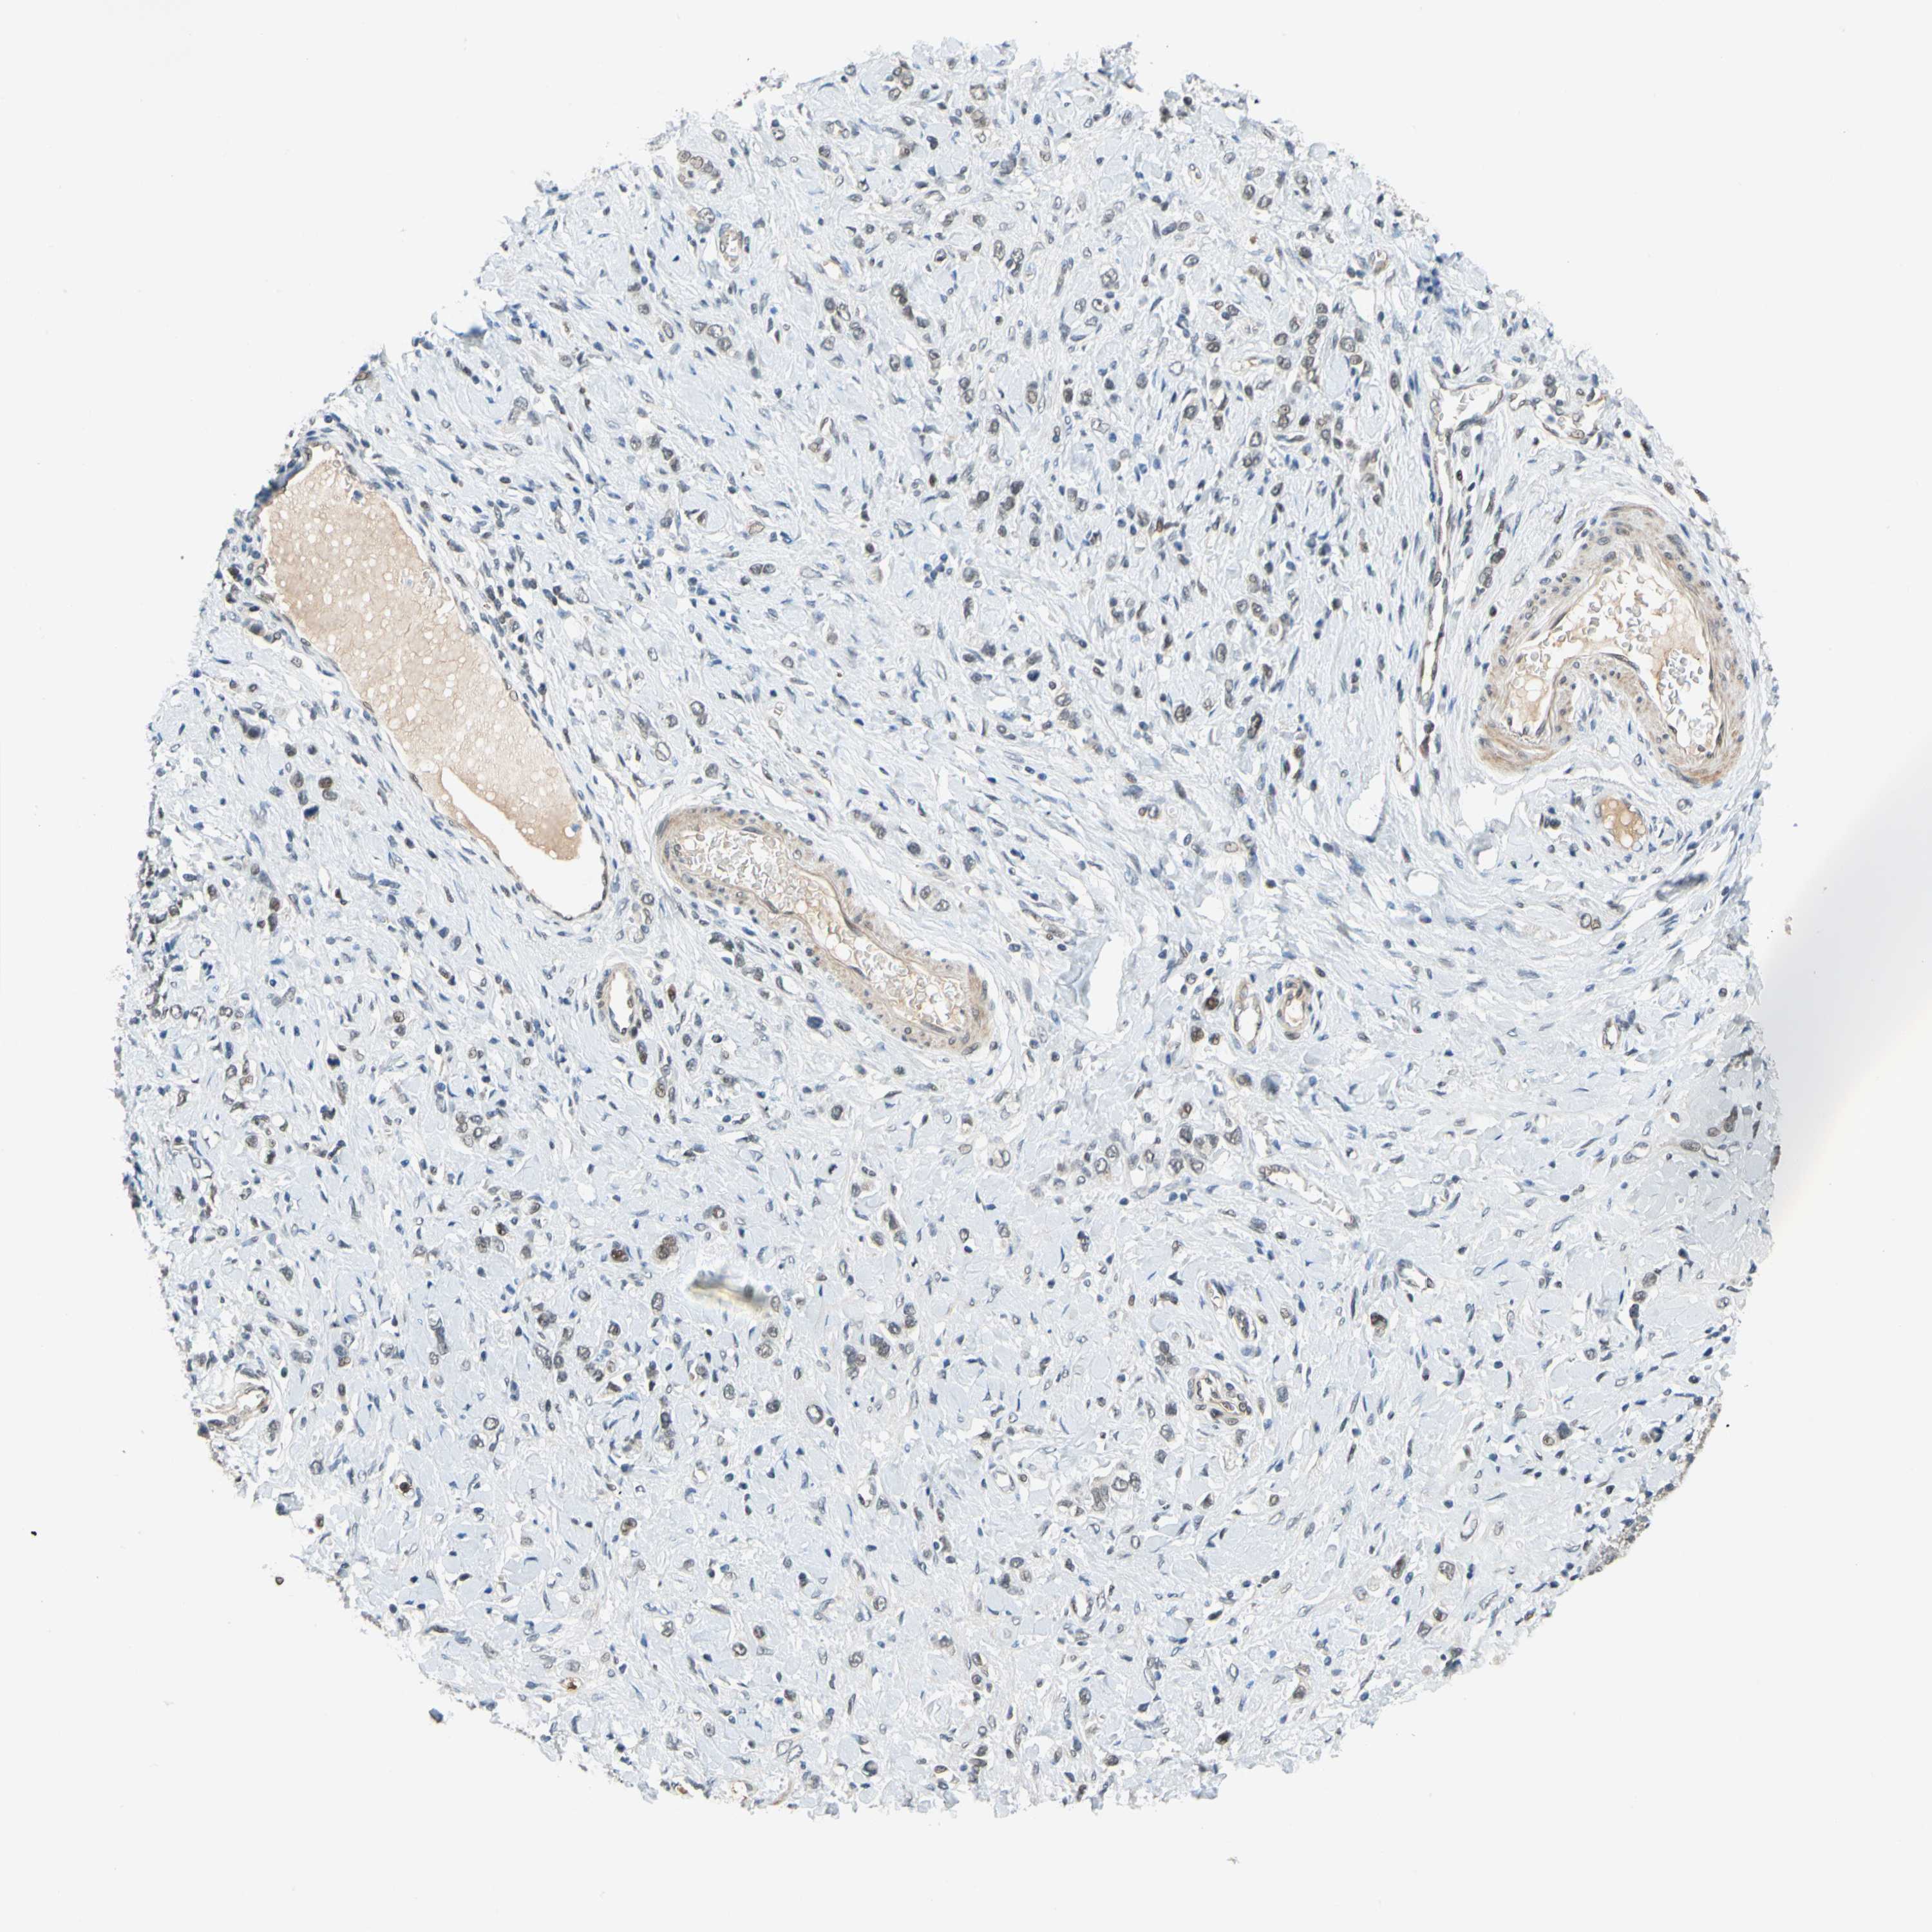

STOMACH CANCER - Protein expressioni

A mouse-over function shows sample information and annotation data. Click on an image to view it in a full screen mode. Samples can be filtered based on level of antibody staining by selecting one or several of the following categories: high, medium, low and not detected. The assay and annotation is described here.

Note that samples used for immunohistochemistry by the Human Protein Atlas do not correspond to samples in the TCGA dataset.

Antibody stainingi

Antibody staining in the annotated cell types in the current human tissue is reported as not detected, low, medium, or high, based on conventional immunohistochemistry profiling in selected tissues. This score is based on the combination of the staining intensity and fraction of stained cells.

Each image is clickable and will lead to virtual microscopy that enables deeper exploration of all samples and also displays staining intensity scores, fraction scores and subcellular localization as well as patient and tissue information for each sample.

Antibody HPA006800

Antibody HPA008781

Staining

High

Medium

Low

Not detected

Intensity

Strong

Moderate

Weak

Negative

Quantity

>75%

75%-25%

<25%

None

Location

Nuclear

Cytoplasmic/membranous

Cytoplasmic/membranous,nuclear

Adenocarcinoma, NOS